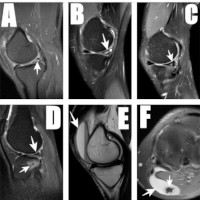

Magnetic Resonance Imaging of Internal Derangements and Other Knee Pathologies in Adult Nigerians

Bukunmi Michael Idowu, Babalola Ishmael Afolabi, Stephen Olaoluwa Onigbinde, Oghenetejiri Denise Ogholoh, Nkem Nnenna Nwafor , Tolulope Adebayo Okedere

Abstract 788 | PDF Downloads 275 HTML Downloads 718 | DOI https://doi.org/10.60787/nmj.v64i4.334

Page 569 - 581

DOI: https://doi.org/10.60787/nmj.v64i4.334